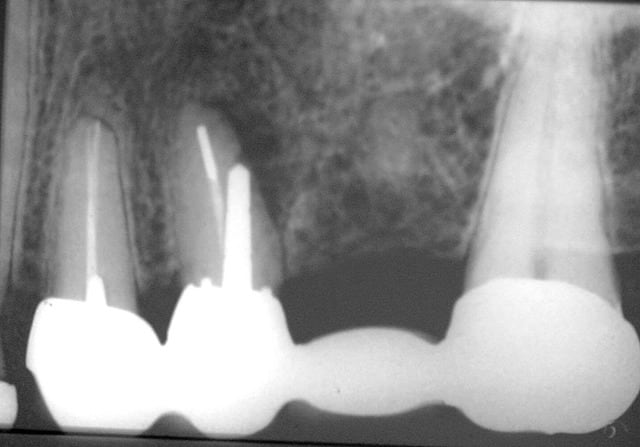

Capture d  cran 2015 03 12 12.28 - Eugenol